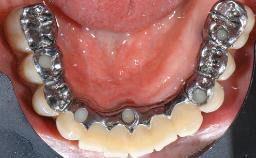

This case describes the ongoing management of a 64-year-old healthy, non-smoking female patient with erosive oral lichen planus (OLP) affecting the gingivae and the buccal and lingual mucosa. The peri-implant mucosa was also affected subsequent to implant placement. The patient had osseointegrated implants (four in the maxilla, four in the mandible) placed following extraction of hopeless teeth and a healing period. The patient had a history of OLP prior to implant placement and had been referred to an oral-medicine specialist for definitive diagnosis and treatment. She exhibited generalized oral mucosal involvement. Following a clinical assessment, biopsy, and blood tests, she was treated with topical corticosteroids. Systemic prednisolone was reserved for severe flare-ups. Amphotericin lozenges were used in combination with corticosteroid treatment to prevent the development of oral candidiasis.

Retention Screw-retained, with 4 or more splinted implants Screw-retained, with 4 or more splinted implants